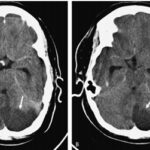

Los estudios de TC permiten evidenciar los accidentes cerebrovasculares (ACV) ocasionados por el abuso de la cocaína. Por caso, se localizó en la literatura imágenes que permiten ver el ACV isquémico agudo de la arteria cerebral media izquierda de un paciente. La TC sin contraste intravenoso visualiza la hipodensidad de la cabeza del caudado, del núcleo lenticular y de la ínsula izquierda. También se realizaron estudios de RM, que permiten observar la restricción del área isquémica en el territorio silviano(18) (ver Imagen 5).

Los consumidores habituales de cocaína suelen tener un pico de presión arterial sistólica elevada y un aumento de la frecuencia cardíaca tras el consumo, que los hace propensos a sufrir malformaciones arterovenosas. Al mismo tiempo, si esta sustancia se combina con etanol, las probabilidad de padecer una hemorragia subaracnoidea se incrementan. A propósito, se puede mencionar el caso de una paciente de 33 años de edad con síntomas de cefalea intensa y hemiparesia izquierda, en cuyo análisis de tóxicos de orina se detectó cocaína.(18)

En el caso que se viene reseñando, se realizó TC sin contraste para evidenciar eventuales daños isquémicos. En este estudio se localizó un hematoma intraparenquimatoso (ver Imagen 6). Este tipo de hematomas tiene un significativo riesgo para la persona, dado que puede avanzar hacia hemorragias con daño en la barrera hematoencefálica e incremento de la presión intracraneal, que puede ocasionar déficit neurológico e incluso la muerte.(17, 18)